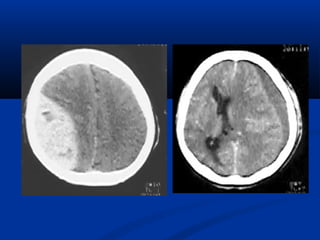

U maùu vuønghaømU maùu vuøng haøm (T)/(T)/ Daõn tónh maïchDaõn tónh maïch caûnh ngoaøi (T)caûnh ngoaøi (T)

Xaùc ñònh vò tríxöông söôøn treân CT